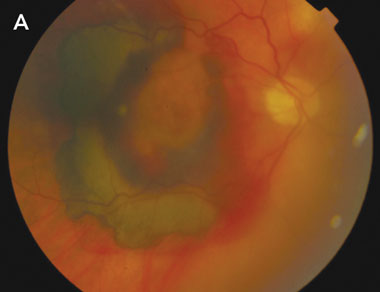

A: Fundus photograph of the right eye at presentation, showing macular subretinal and intraretinal haemorrhage. The mild haziness of the photograph is indicative of vitreous haemorrhage. |

Development of large subretinal and vitreous haemorrhages in neovascular AMD is uncommon. Treatment options are limited and, even with surgical intervention, visual outcomes are in the range of light perception to counting fingers only, with significant loss of paracentral and peripheral vision.4 The functional effects are therefore profound.

Previous studies have demonstrated an association between the use of anticoagulant medication, particularly warfarin, and large intraocular haemorrhages among patients with neovascular AMD.5,6 The largest of these, a retrospective case–control study comprising 100 patients, found that those with massive intraocular haemorrhage were 11.6 times more likely to be taking anticoagulant medication.6 Among these patients, INR ranged from 3.0 to 4.0. Patients with massive haemorrhage were twice as likely to be taking aspirin, although the significance of this finding is less certain, as the lower limit of the 95% confidence interval was less than 1. No patient was taking anticoagulants and aspirin concurrently.6

In our patient, the role of concurrent aspirin therapy is unclear, as there is no evidence in the literature to support or refute the hypothesis that concurrent antiplatelet therapy may have contributed to the development of haemorrhage. However, both instances of haemorrhage were noted to occur at times when his INR was high compared with those recorded over the previous 12 months. Our patient was taking aspirin at all times during this period. Although it is possible that intraocular haemorrhage may have occurred purely as a result of his underlying neovascular AMD, the temporal relationship between the development of the haemorrhages and the high INRs strengthens the case for the implication of warfarin therapy as a contributing factor. Application of the Naranjo probability scale7 indicates that this adverse drug event was probable (Naranjo score, + 5).